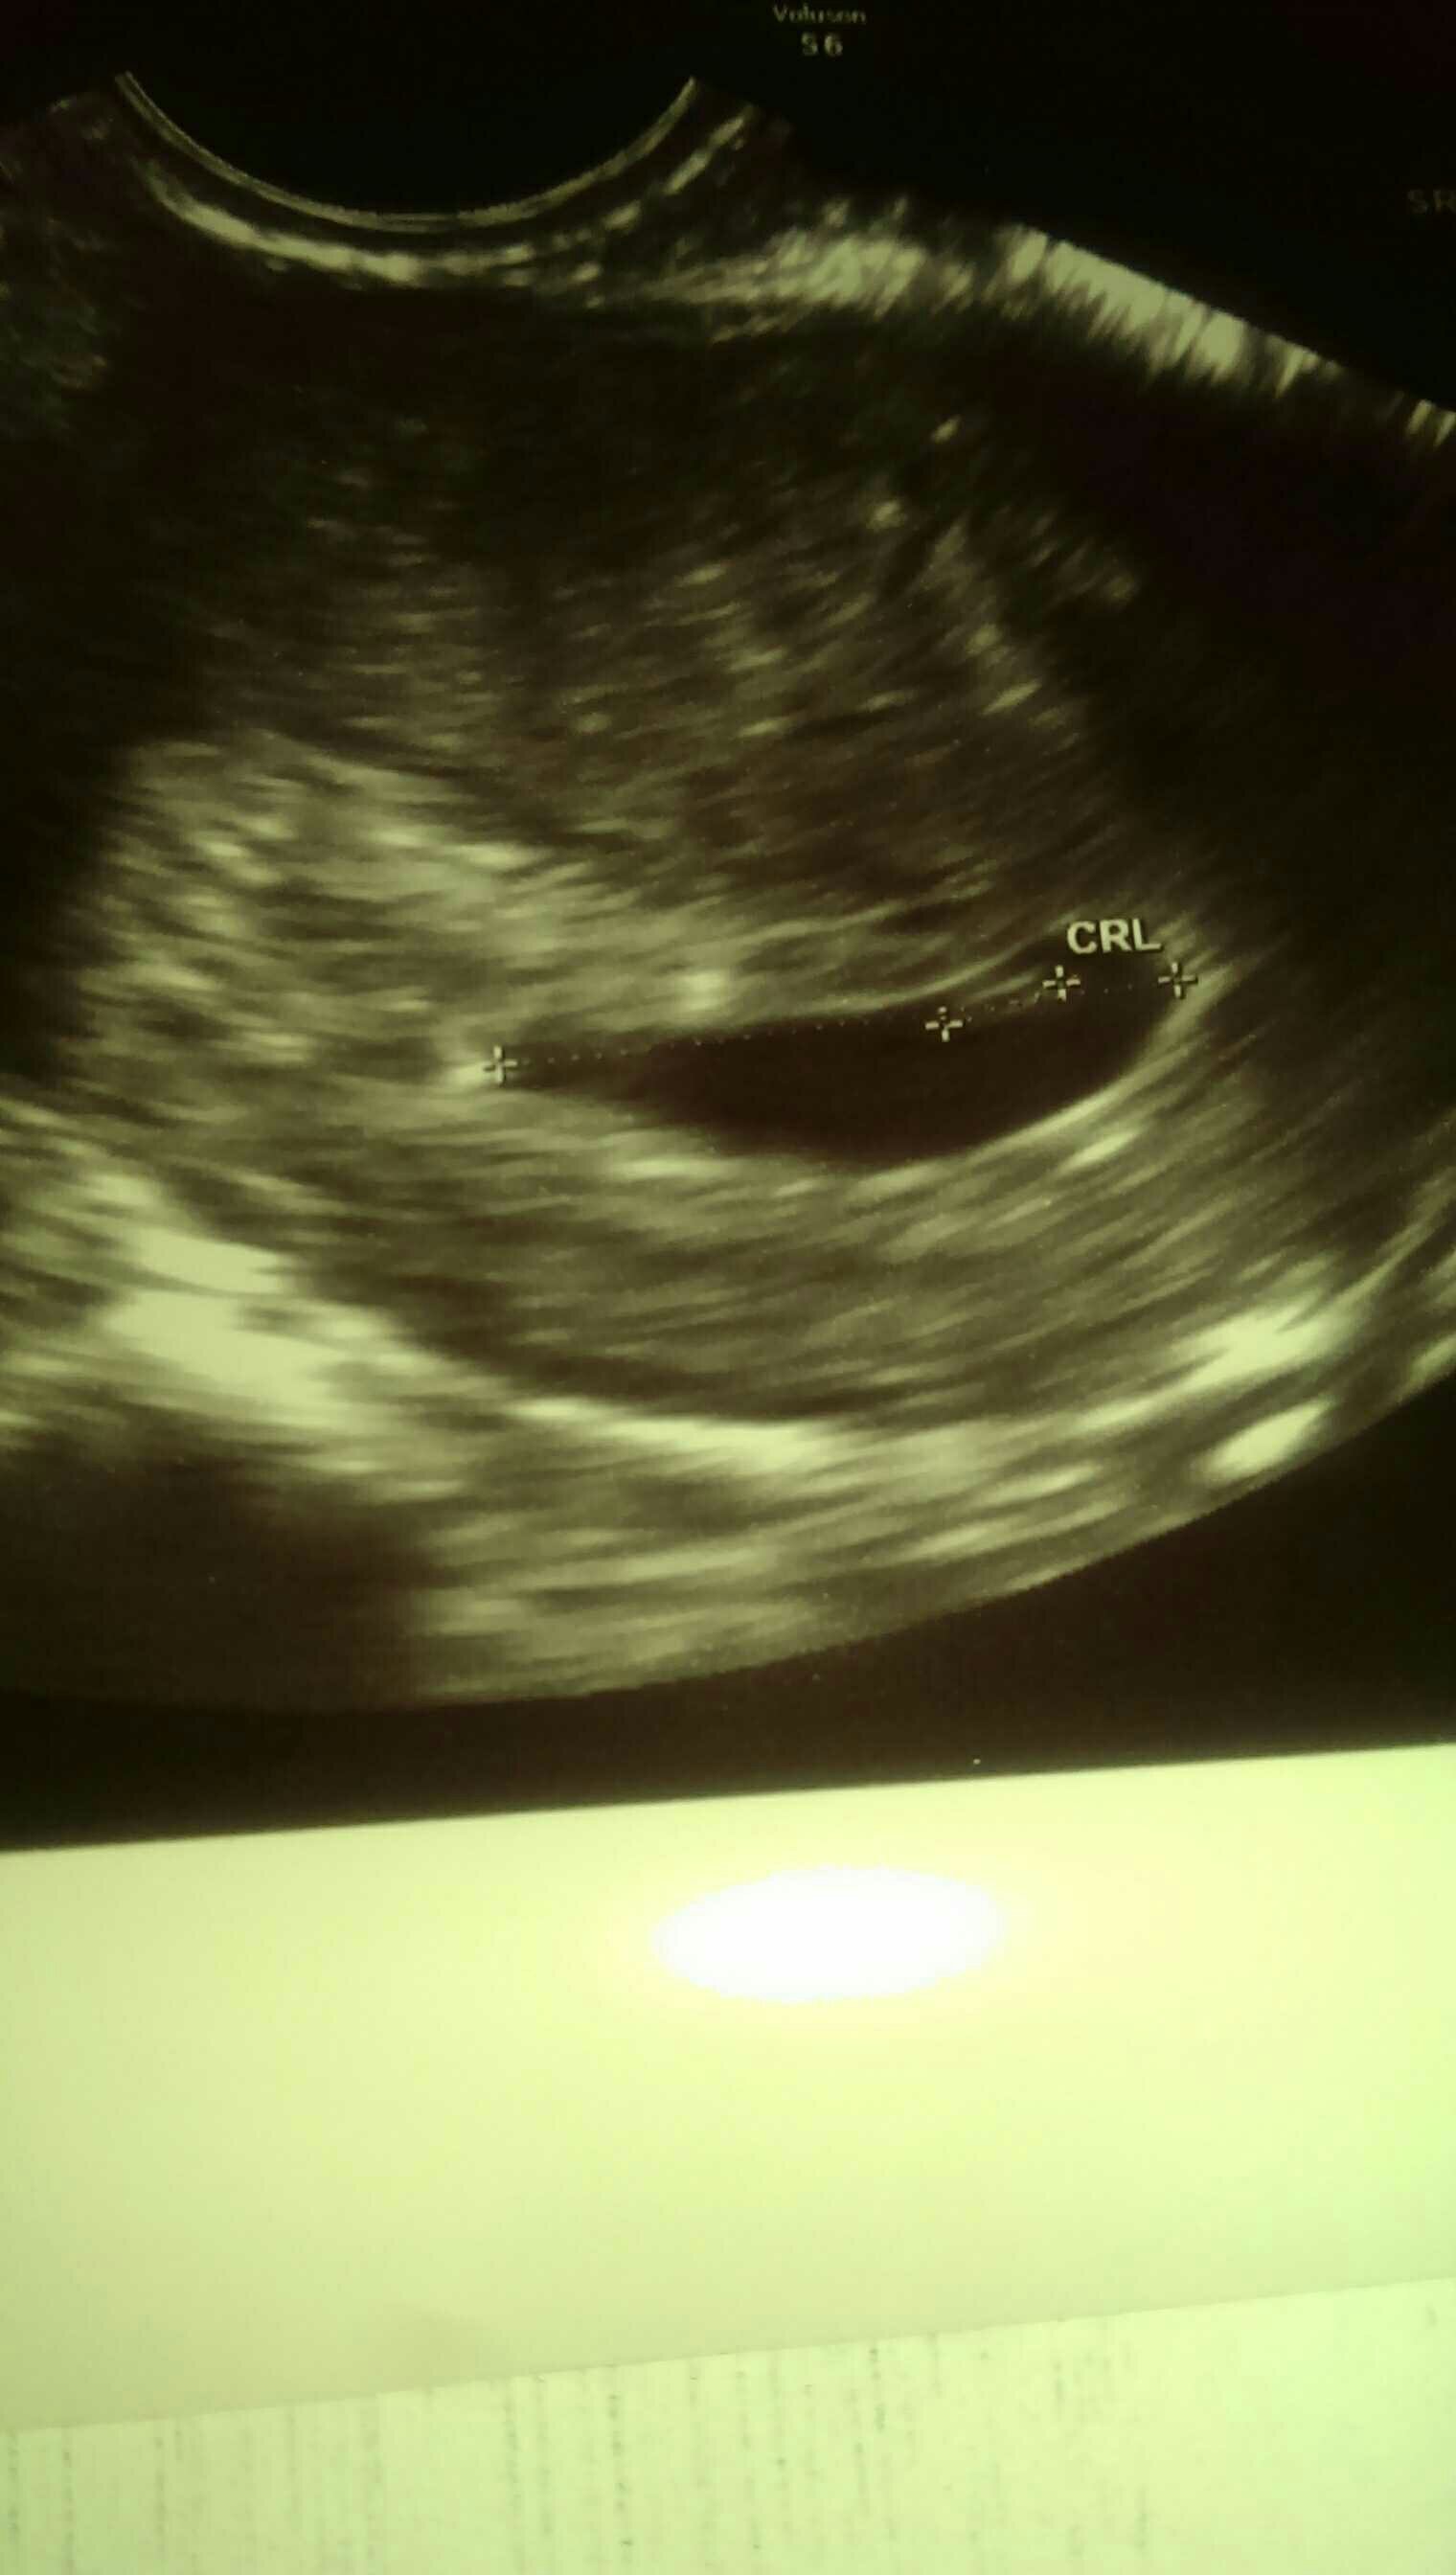

To i moja kolej. Na chwilę obecną spodziewam się bliźniąt jednojajowych! Mają po 3 mm i jednemu już bije serduszko. Za dwa tygodnie wizyta kontrolna i założenie karty ciąży. Oby wszystko było dobrze. A tu zdjęcie. Przy pecherzyku żółtkowym widać dwa malutkie przecinki jeden pod drugim